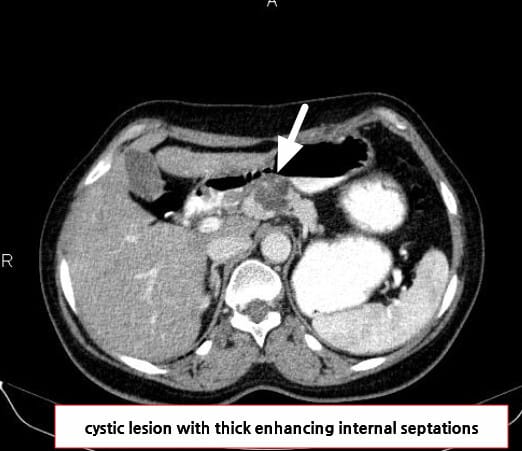

영상 소견

벌집 모양(microcystic) 낭종, Central scar, 석회화 등

| 🟦 Microcystic pattern |

| 수 mm 크기의 다수의 낭종이 집합된 형태입니다. |

| 🟦 Central scar with calcification |

| 중심에 석회화를 포함한 반흔이 특징적으로 관찰됩니다. |

Niknejad M, Pancreatic serous cystadenoma. Case study, Radiopaedia.org (Accessed on 18 Jul 2025) https://doi.org/10.53347/rID-85866